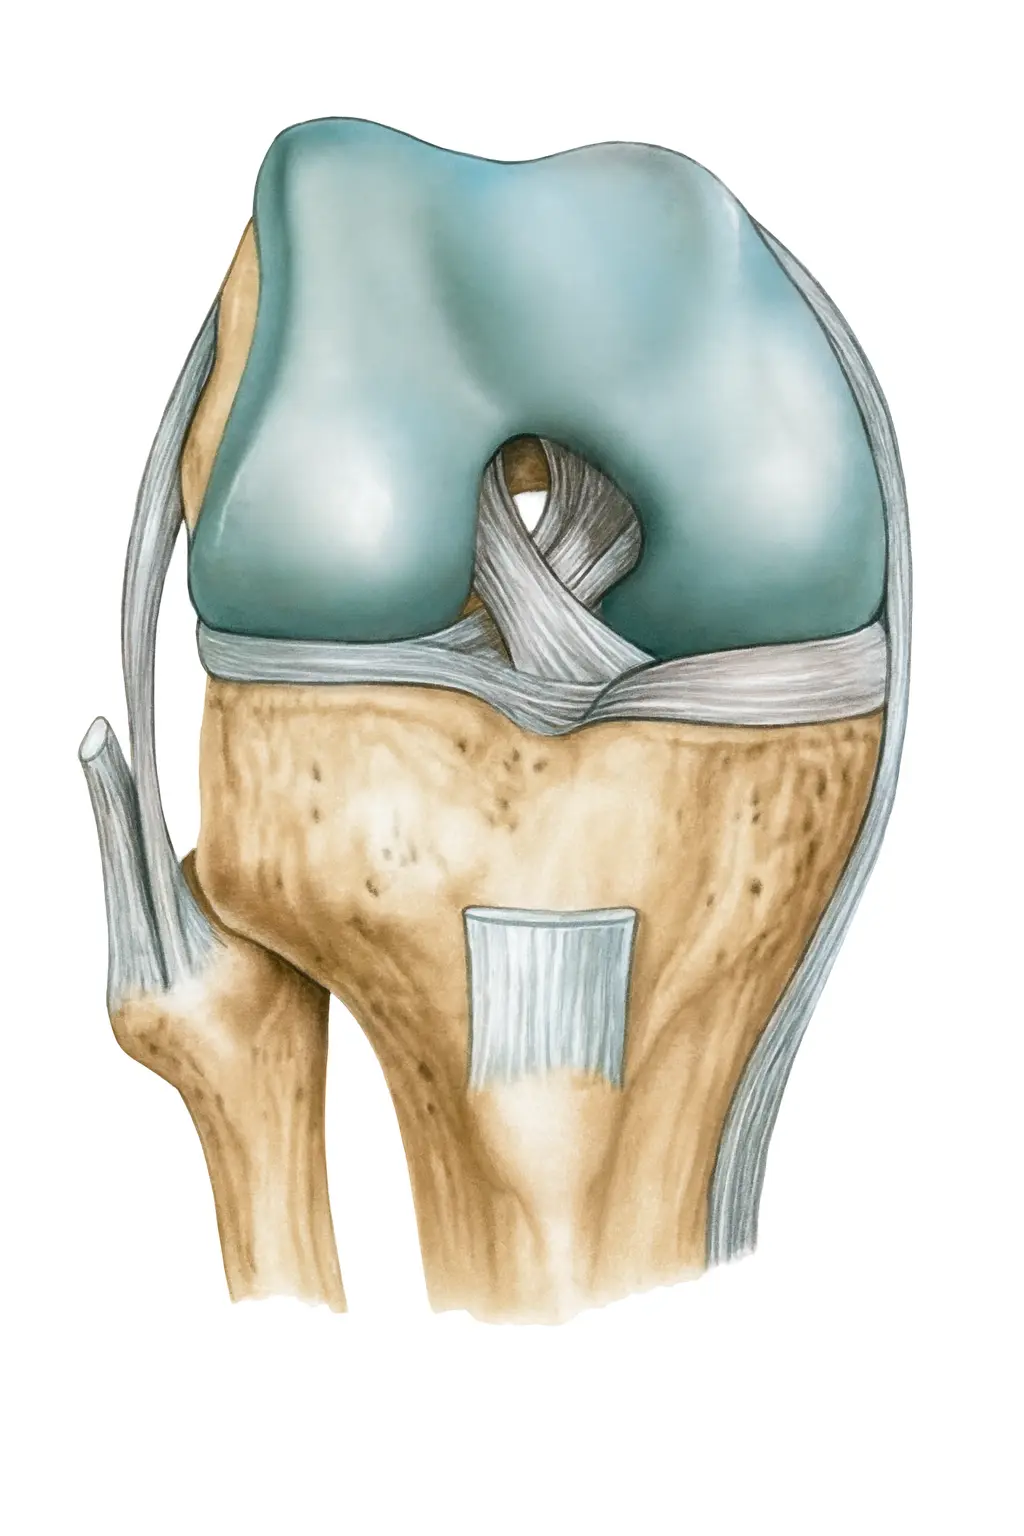

█什麼是十字韌帶斷裂?

前十字韌帶(ACL)是膝蓋裡的重要穩定結構,主要功能是防止脛骨向前滑動並控制旋轉。

當ACL斷裂時,膝蓋容易出現「卡住」或「軟腳」的狀況,長期下來會影響日常生活與運動表現。

█十字韌帶斷裂的分級與嚴重程度

●部分撕裂

韌帶仍有連續性,膝蓋穩定性下降有限,透過保守治療與肌力訓練,有機會恢復日常生活功能。

●完全斷裂

韌帶斷成兩段,膝蓋穩定性大幅下降。進行急停、轉向、跳躍等動作時風險極高,容易導致二次受傷。